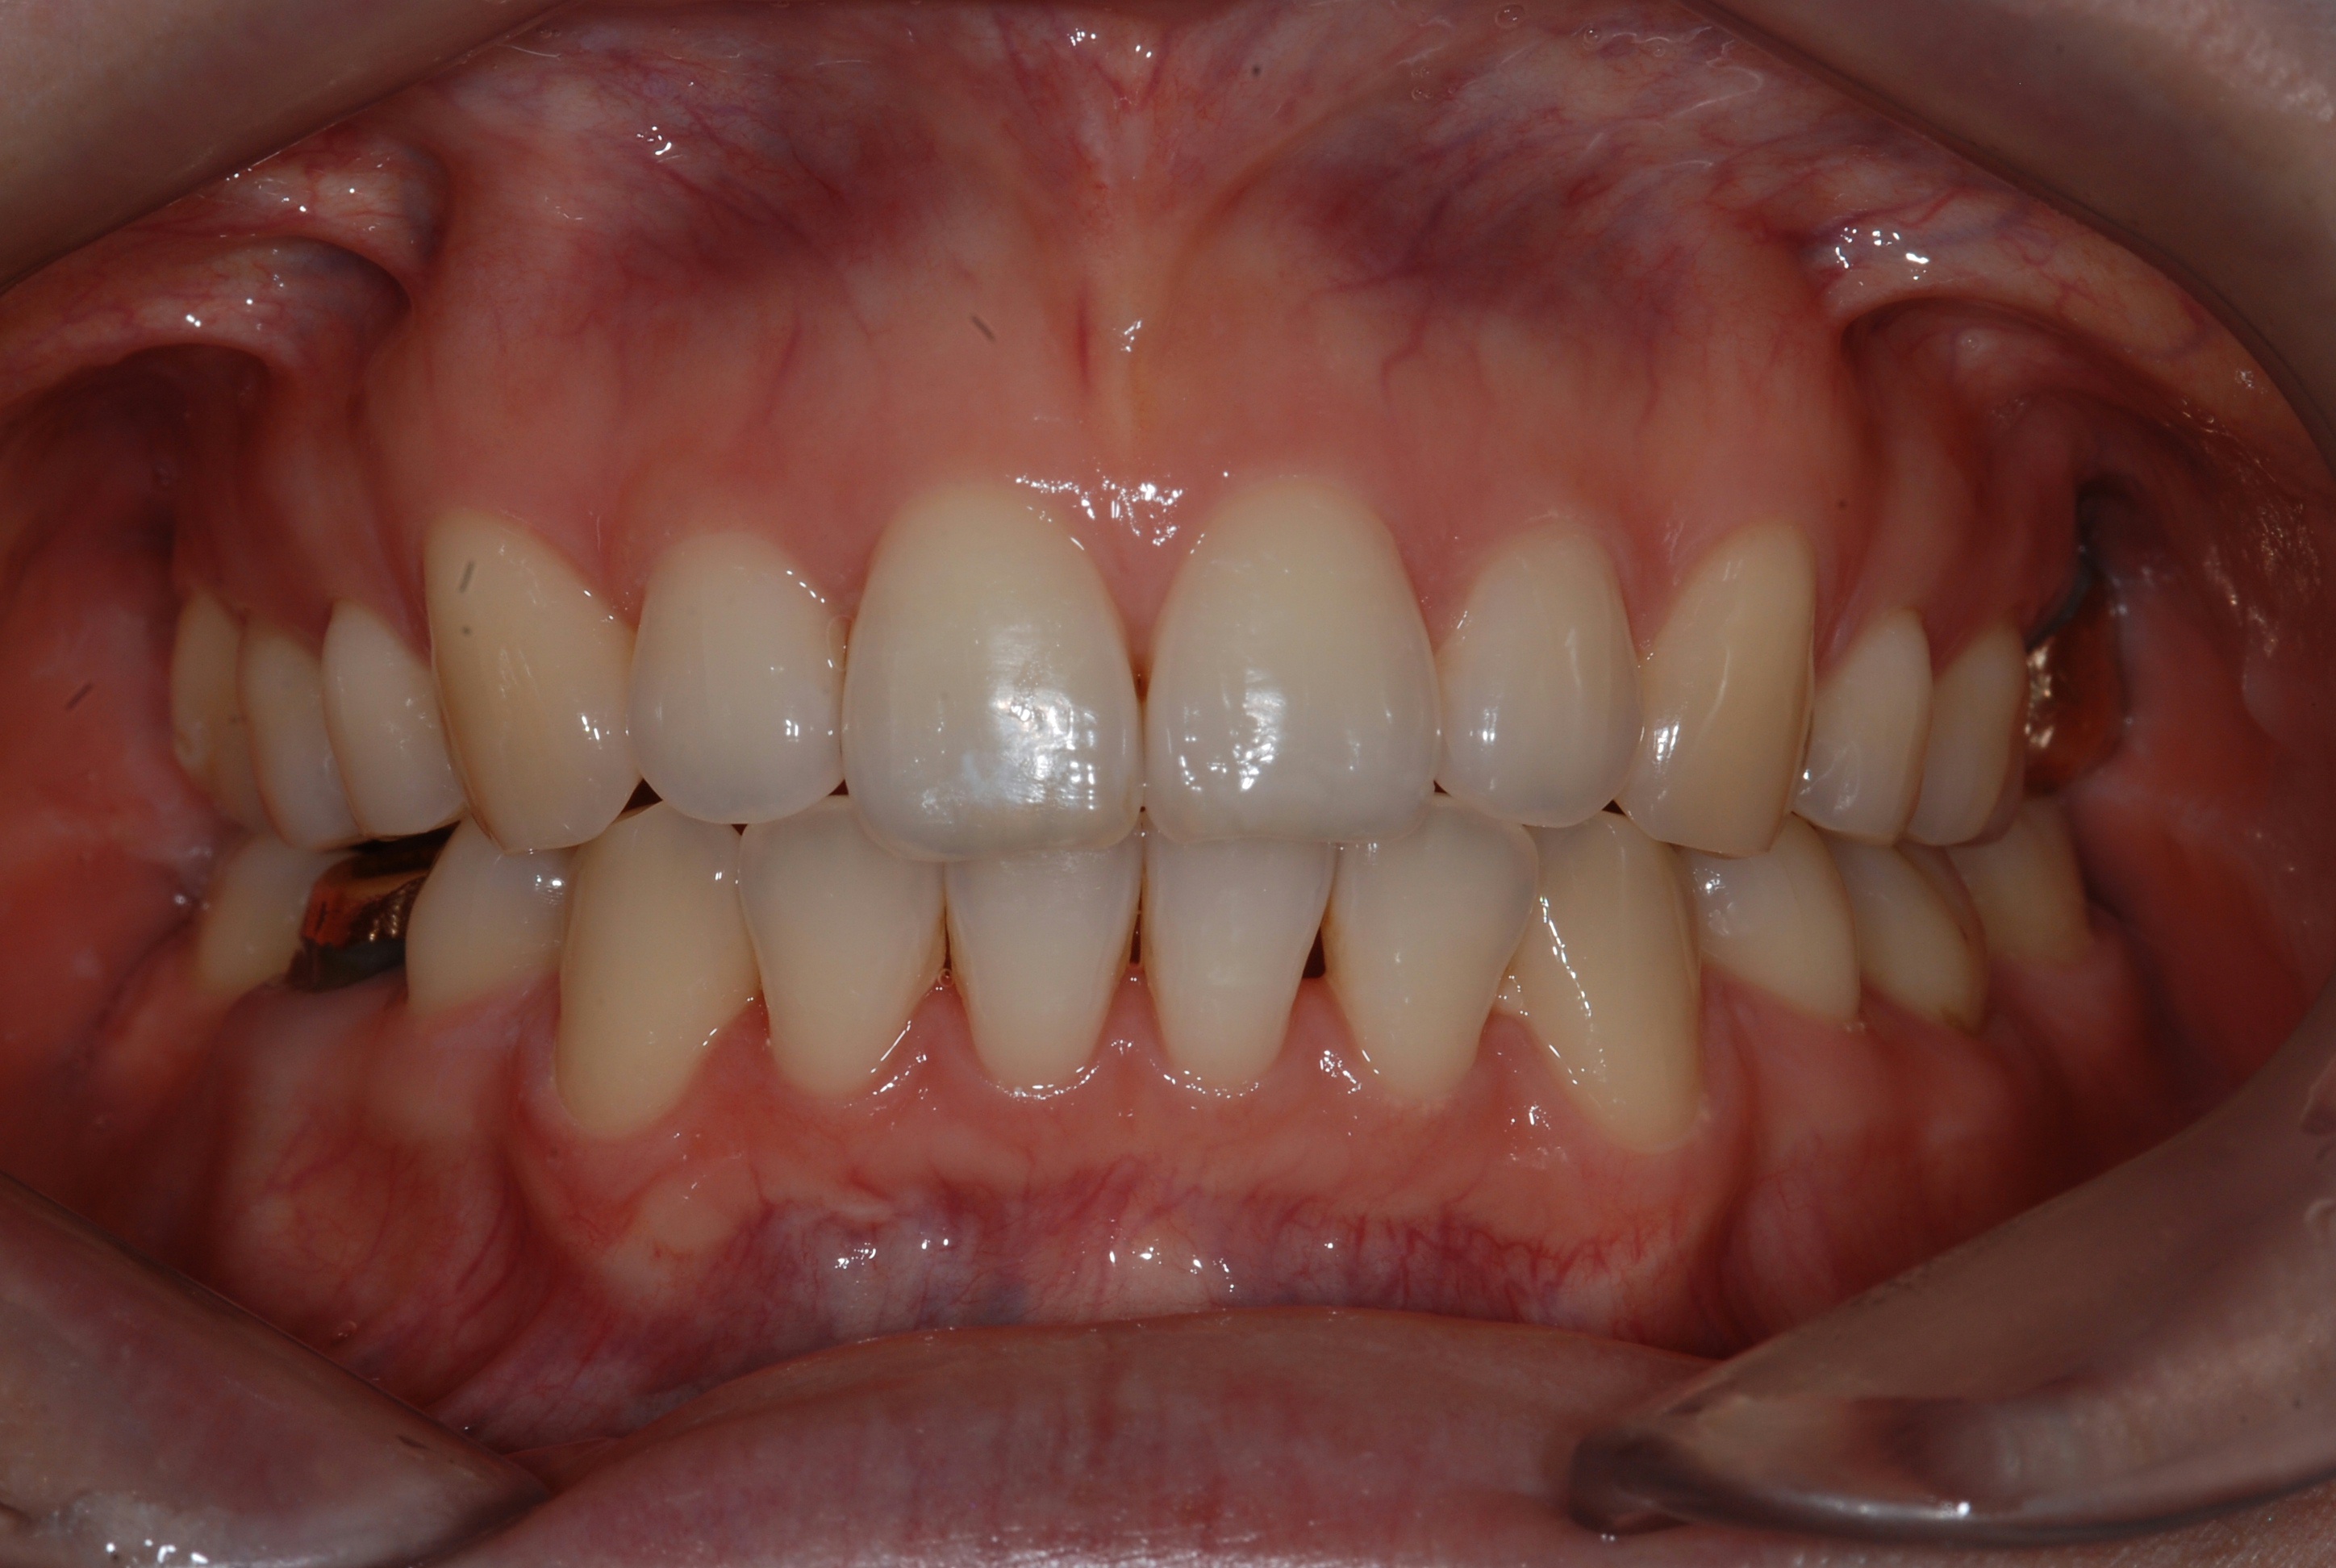

치료 후 사진입니다.